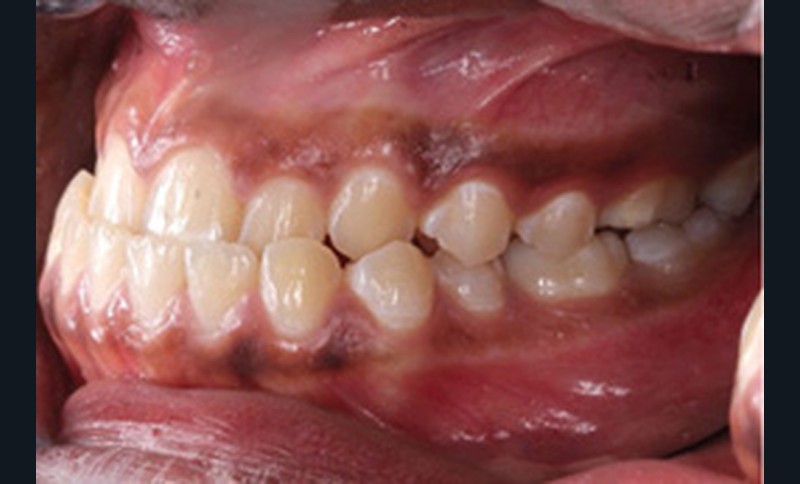

Examen clinique (fig. 1a-h)

À l’examen de face, Anisa présente un visage ovalaire, des hémifaces symétriques, des lignes horizontales parallèles, une augmentation de l’étage inférieur, une occlusion labiale légèrement forcée et des dents mandibulaires exposées au sourire. Les profils général et sous-nasal sont concaves avec un angle naso-labial augmenté et une prochéilie inférieure.

L’examen clinique endo-buccal révèle une denture adulte jeune avec un inversé d’articulé antérieur de 13 à 23, des tatouages gingivaux ethniques et des taches de décalcifications, un parodonte sain mais un brossage insuffisant.

L’arcade maxillaire est en V et la voûte palatine profonde. L’arcade mandibulaire a une forme en U (non-concordance des formes d’arcade) et présente des malpositions des dents cuspidées. La médiane mandibulaire est décalée à gauche de 2 mm ; le recouvrement antérieur est de 2 mm ; les molaires sont en classe III avec un surplomb inversé.